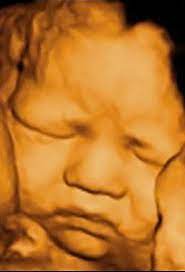

TOP BEST 3D/4D ULTRASOUND IMAGING CENTRE IN SECTOR 8 ROHINI